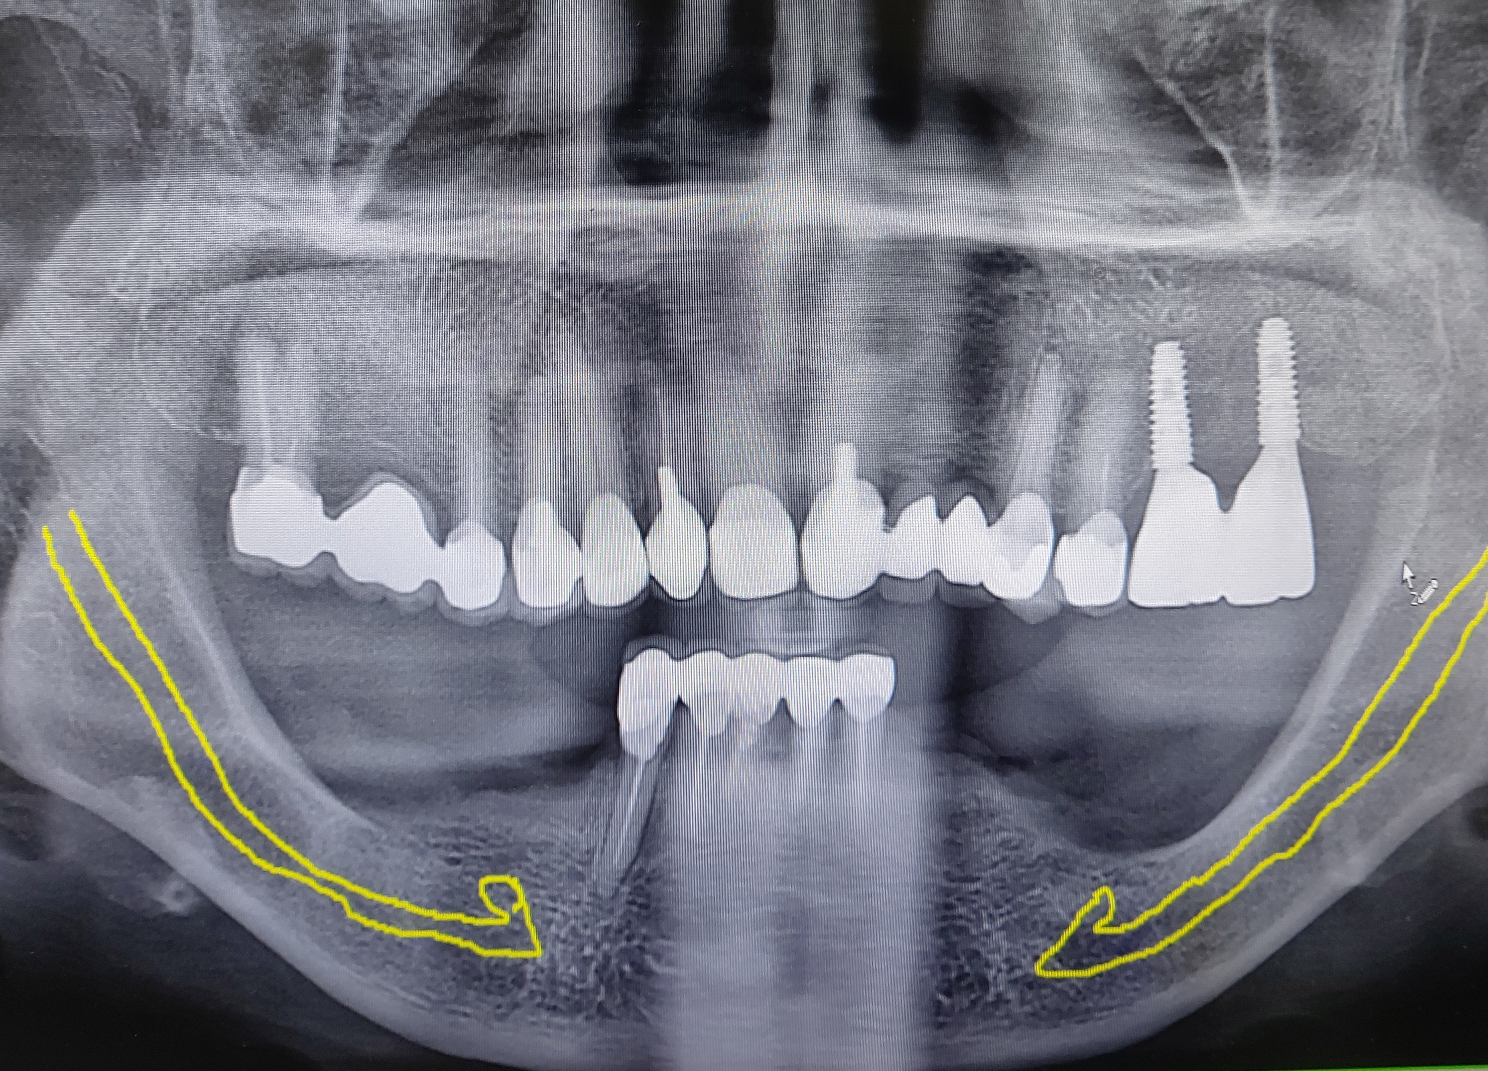

일반적으로 심하게 퇴축된 하악 구치부에서는 위에 보이는 노란선처럼 하치조 신경관이 주행하고 있어서 실제로 임플란트를 심을때 해부학적 장애로 작용합니다.

일반적인 임플란트는 최근 5 mm 정도의 길이의 특수 임플란트도 나오고 있지만 임상적 경험상 7 - 8 mm 이상의 길이의 임플란트를 식립할려고 노력합니다.